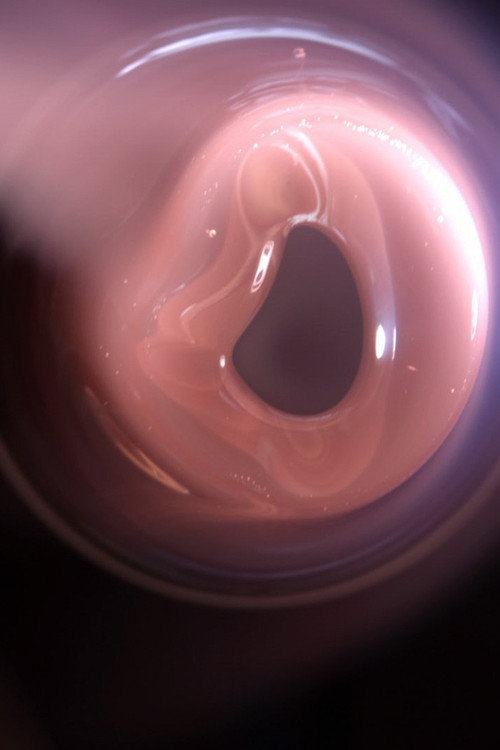

Haptic Skins of a Glass Eye (2015)

Haptic Skins of a Glass Eye